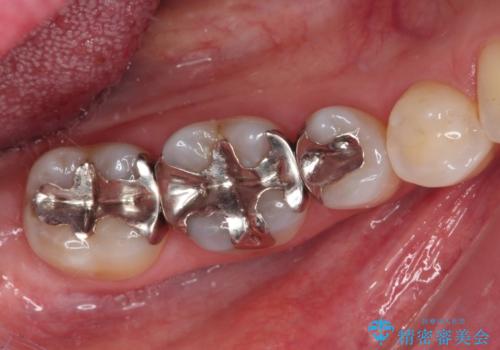

- 銀歯をセラミックにしたいとのことで来院された患者様です。

それを左右に分けて行いました。